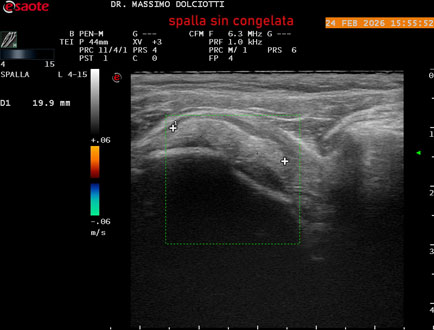

Data inserimento: 02/03/2026

Ecografia del: 24/02/2026

Strumento: Esaote MyLab Eight

Sonda: Lineare Multifrequenza 4-15 MHz

Età Paziente: F 71 anni

Motivazione dell'esame: da 1 mese dolore alla spalla sinistra, anche di notte.

Commento all'esame: le immagini ed il video documentano il tendine sovraspinato sinistro spiccatamente disomogeneo, per presenza di immagine iperecogena, delle dimensioni di 21 x 4 mm, da ricondurre a estesa calcificazione. Quadro clinico di spalla congelata.

Conclusioni: spalla sinistra congelata (frozen left shoulder).